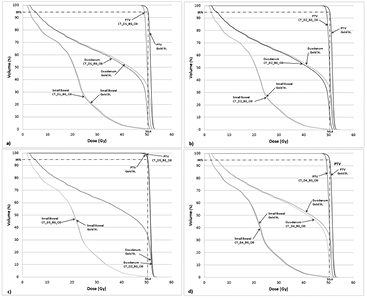

The effect of uniform rED assignment on the target D95% and D5% for CT- based pancreas IMRT plan quality were ⩽3% of Gold St (table 5). The variation in pancreas D95 was found to be at most 3.0% for CT-based IMRT plans. Changing the value of NST and PTV resulted in comparable variations in D95% (−3.0%, −2.5% and −2.7% for type1, type2 and type4 assignment, respectively). However, a homogeneous water rED (type3) assignment for all structures (i.e. target, NST and OAR) resulted in the smallest variation in D95% (0.2% higher than the Gold St). The shapes of DVH for the PTV are similar to one another for all types of rED assignment on CT-based plans (figure 1). The variation in D5% was found to vary in magnitude by −2.0%, −1.4%, 0.3% and −1.8% for type1, 2, 3 and 4 rED assignments).

Figure 1. Pancreas IMRT dose volume histogram (DVH) for a representative case (anonymized patient panc2) for the following different relative electron density assignments: (a) CT_D1_B0_O0; (b) CT_D2_B0_O0; (c) CT_D3_B0_O0 and (d) CT_D4_B0_O0. Note each panel depicts the DVHs of the PTV, duodenum and small bowel of the given rED plan together alongside the same structures from the gold standard (i.e. planning CT).

Standard image High-resolution imageThe impact of uniform rED assignment on plan quality for the duodenum, small bowel, stomach and kidneys on CT-based plans was found to be <4% (table 5). The largest variation seen in pancreatic OAR was for the duodenum, where maximum variations of −3.7 and −3.0 were found for forced rED assignment type1 in Dmax and Dmean, respectively. Smaller variations were found for the homogeneous water assignment (CT_D3_B0_O0). The variations seen in the small bowel, stomach, and kidneys were found to be no larger than −2.3% compared with the Gold St.